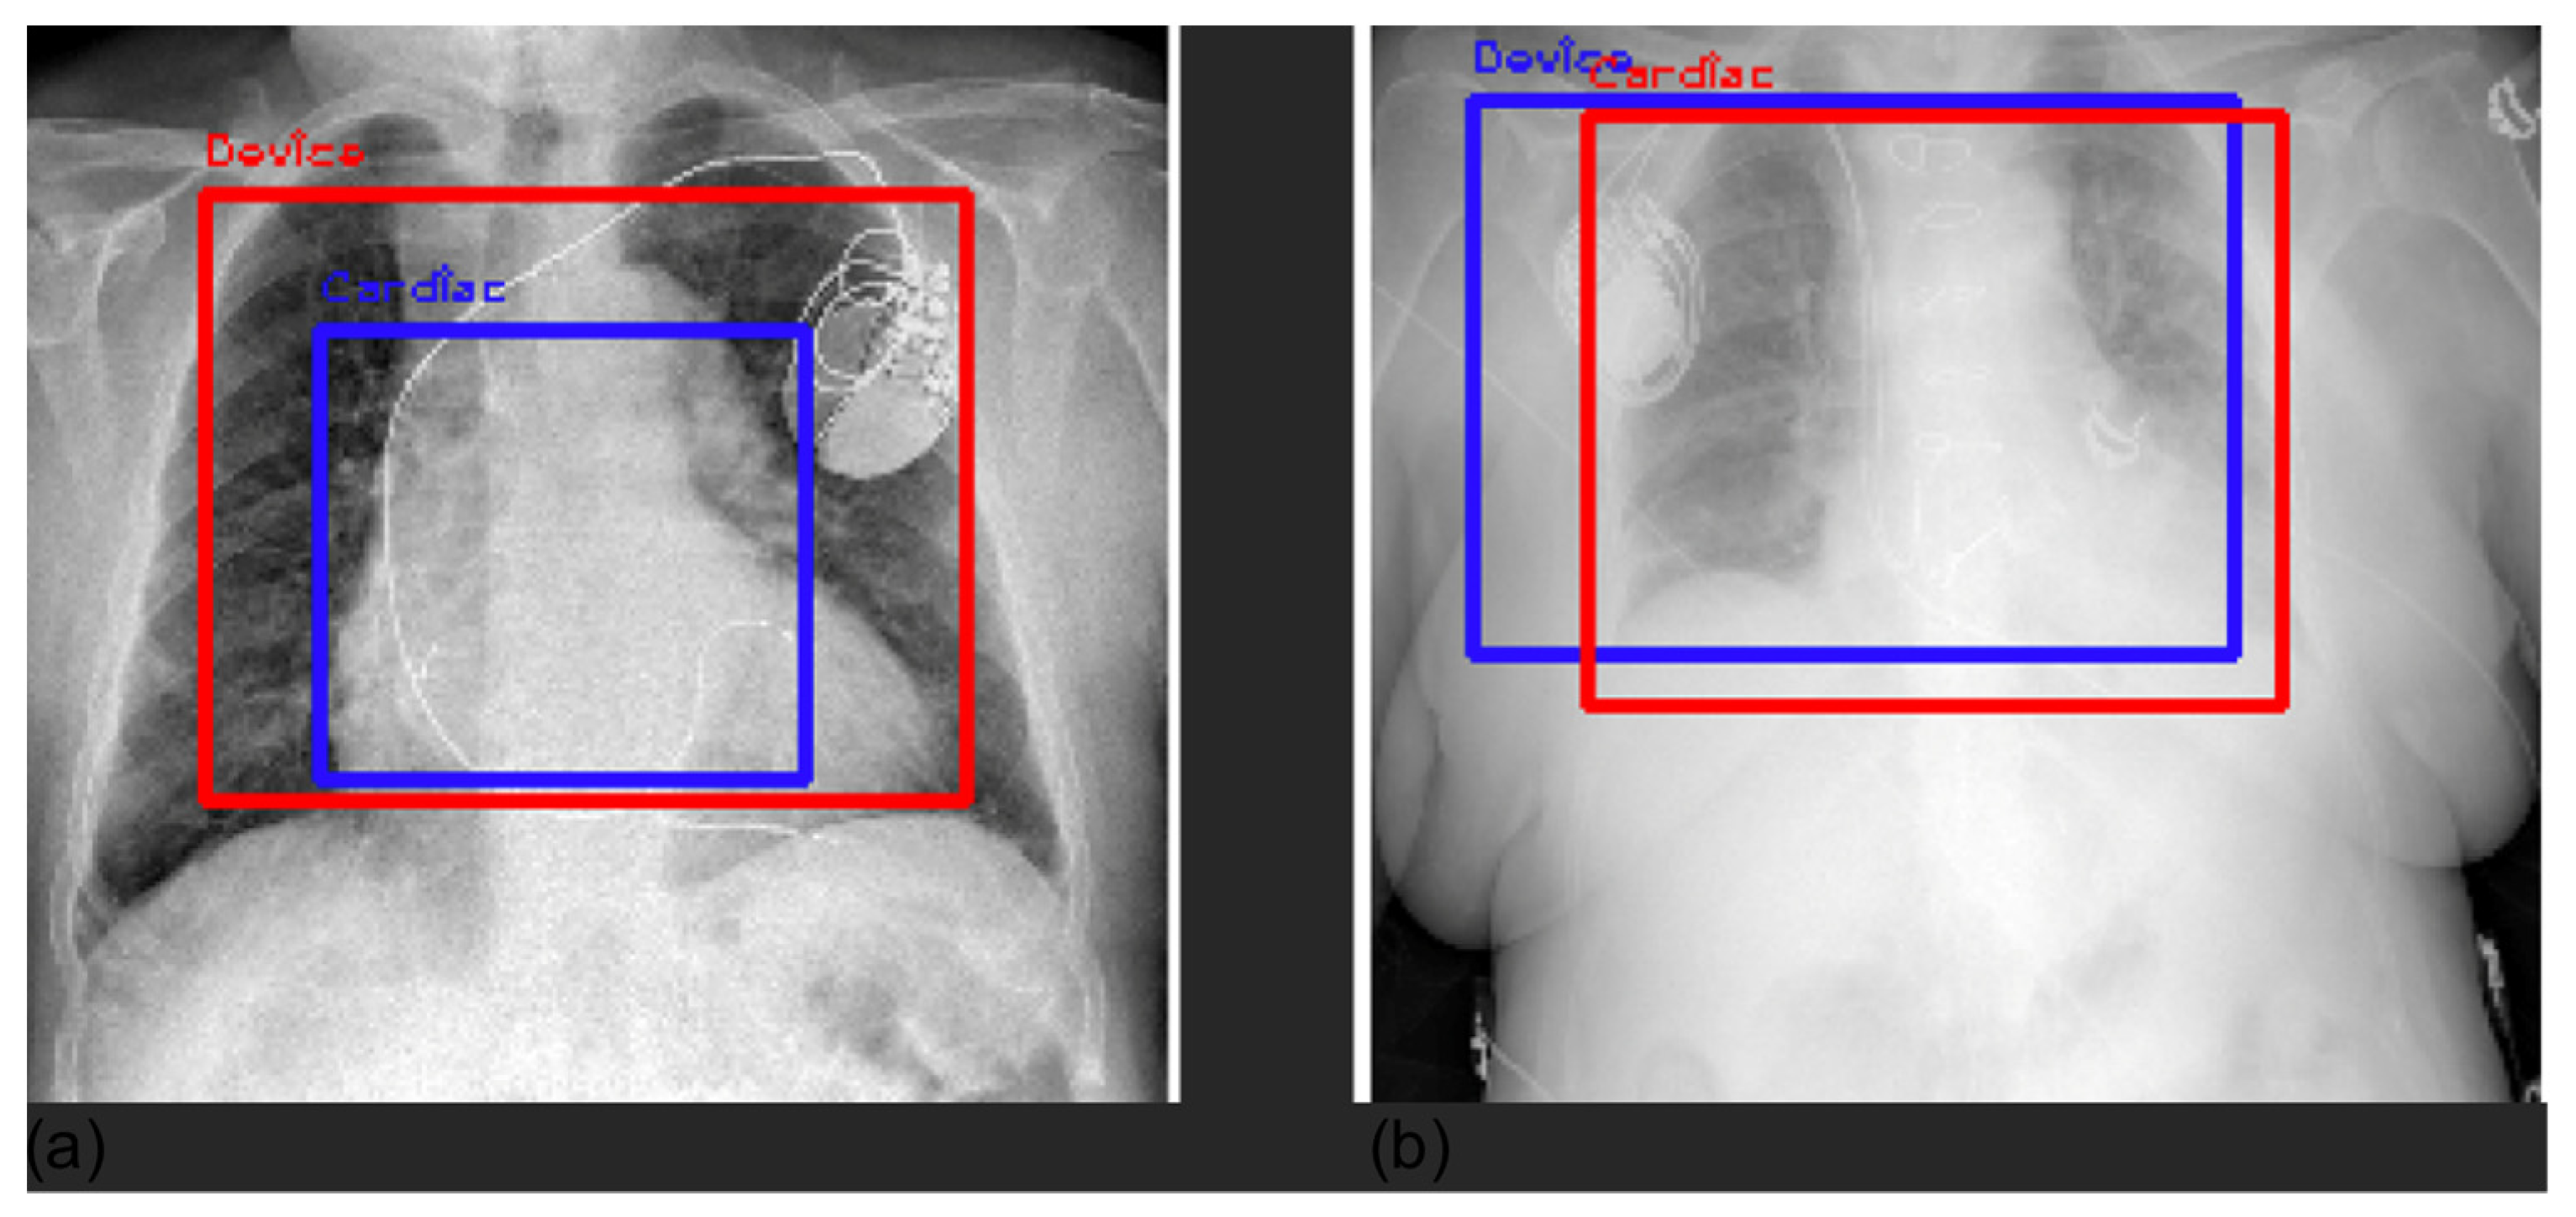

In Figure 8, we superimposed the bounding boxes for two classes to show how the model looks at different input areas depending on the specific class.

Figure 8.

Superimposition of bounding boxes for cardiac (panel a, cardiac in blue and device in red) and device (panel b, device in blue and cardiac in red) outcomes for two examples.

Furthermore, we compared Grad-CAM maps with saliency masks extracted by a radiologist in terms of common area over the full area identified by the expert. Our models achieved an overall average agreement of 75% (80% lung, 65% pleura, 84% cardiac, 75% PNX, and 67% device), showing how the models automatically learned meaningful features from the images similarly to an expert radiologist. Explainable AI (XAI) algorithms for visualization are successful approaches to identify potential spurious shortcuts that the network may have learned. Overall, our CNNs focused on meaningful areas of the image for the respective prediction. We found some inconsistencies in some examples of device predictions, especially with pacemakers. Figure 9 shows an example of a correct classification but based on an area that does not match well the hardware of the CIED.

The saliency map highlights the intracardiac leads as the region responsible for device prediction.

For these reasons, we applied Grad-CAM [26] to our problem, with the aim of (1) interpreting, understanding, and explaining CNN black-box behavior through comprehensible explanations to increase the trust and acceptance in AI for medical imaging for translation to clinical routine; and (2) investigating the presence of potential Clever Hans effects, spurious shortcuts, and dataset biases. Overall, the explanations provided by Grad-CAM showed a satisfactory ability of the model to identify specific markers and features with respect to the identified class. Grad-CAM saliency maps were found inside the lung field, with particular attention to the correct side of the chest. Double-class images correctly showed the differences between chest findings. However, De Grave et al. [27] were skeptical about presenting only a few examples of explanations, as they may not truthfully represent the real behavior of the model. They discussed the need for a population-level explanation to demonstrate the correctness and reasoning of the entire model, in addition to selecting single examples. In this work, we presented randomly selected examples and population-level explanations averaging two batches of 200 CXRs. The averaged saliency maps presented in Figure 3 demonstrate a high level of attention in the center of the image, whereas the borders are almost useless. Our findings demonstrate that the models were generally focused on the lung field without deploying shortcuts and spurious correlations that may be present outside the lung field, such as annotations, different border dimensions, and lateral markers. Overall, examples of local explanations did not indicate the use of shortcuts as the general model. The only exception we identified concerns the device class, particularly when detecting a CIED. Whereas the model generally correctly focused on the hardware components, in some examples (Figure 9), it correctly classified ”device” but exploited the intracardiac leads. This finding is not incorrect, but we would expect the model to focus more on the hardware, i.e., the main box. We believe this might be caused by the original dataset on which the models were pretrained. The device class is extensive and includes lines, tubes, valves, catheters, CIEDs, hardware, coils, etc. However, the percentage proportion of each subclass is not publicly available, so it is possible that “some objects”, such as tubes, leads, electrodes, and catheters, are more present than CIEDs, inducing the model to focus on them. Furthermore, we investigated false-positive predictions with respect to the device class. In most cases, we assert that the model was correctly classified devices, although the ground truth was incorrect. The main reason for such false positives is that our labels were extracted from unstructured medical reports. Whereas diseases are clearly written and discussed in the report, cardiac devices, electrodes, prosthesis, and other “objects” may be omitted in the report because are not considered ”abnormal” as medical pathologies or clinically relevant. We reasonably believe that with further effort in the definition of the ground truth, the performance of “normal” and “device” labels can be improved.